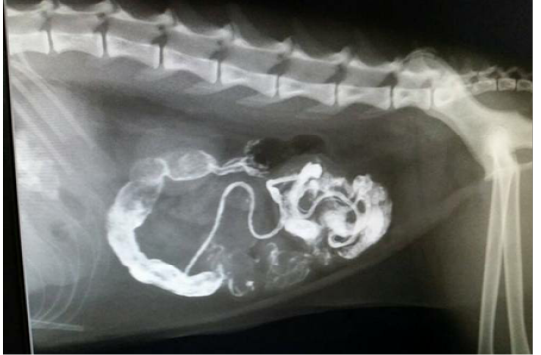

Figure 2

Lateral Radiograph after 20 hours of barium sulphate meal shows streaking of intestinal loop with barium